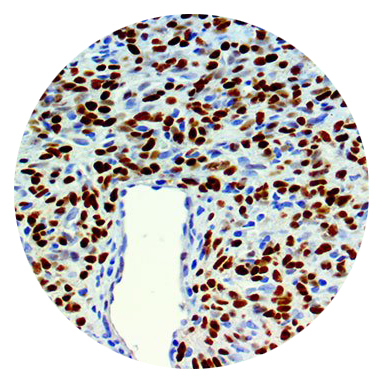

Les tumeurs fibreuses solitaires (SFT) sont des neoplasmes fibroblastiques peu communs. Souvent diagnostiquées par leurs caractéristiques histologiques et une expression fréquente de CD34, ces tumeurs présentent un spectre histologique très large et occasionnellement un immunophénotype inespéré. Par des analyses moléculaires il a été découvert que la plupart des SFT expriment la protéine de fusion NAB2-STAT6. Des études récentes ont suggéré que la détection de STAT6 par IHC est un moyen efficace pour détecter cette protéine de fusion, ce qui fait de STAT6 un marqueur pour les cas de SFT non conventionnels.